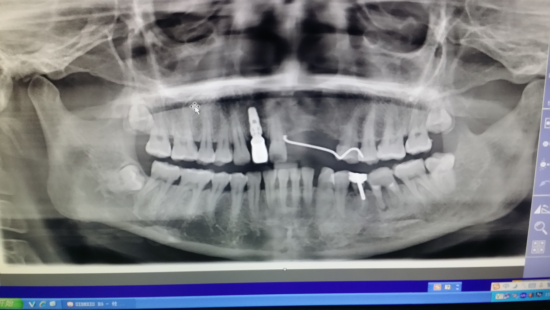

种植牙术后

种植牙术后 (2)